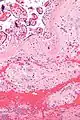

Micrograph of a chronic deciduitis, showing the characteristic plasma cells. H&E stain.

Chronic deciduitis is a type of long-lasting inflammation that arises in pregnancy and affects the endometrial stromal tissue (decidua).

It is associated with preterm labour.[1] The diagnosis rests primarily on the presence of plasma cells.[2]